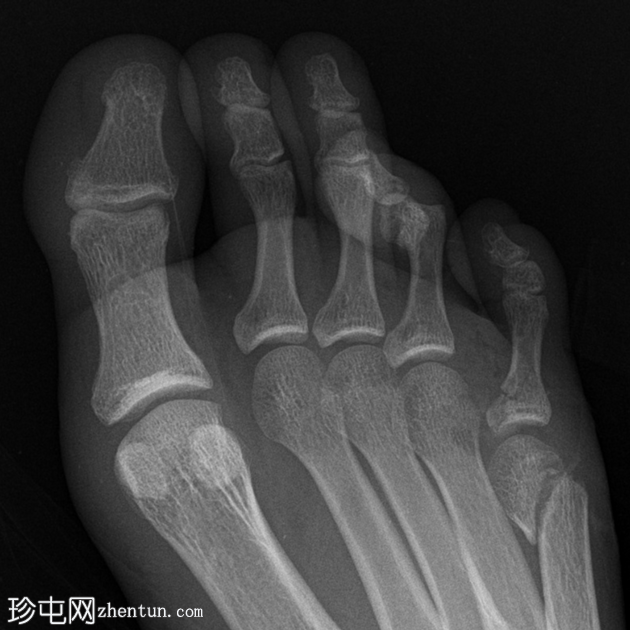

正位

正位(放大)

第四趾近节指间关节(PIPJ)跖侧脱位。

第五趾近节指骨无移位骨折。

第五跖骨颈骨折伴跖侧移位(背侧成角)。

跟骨关节内骨折。